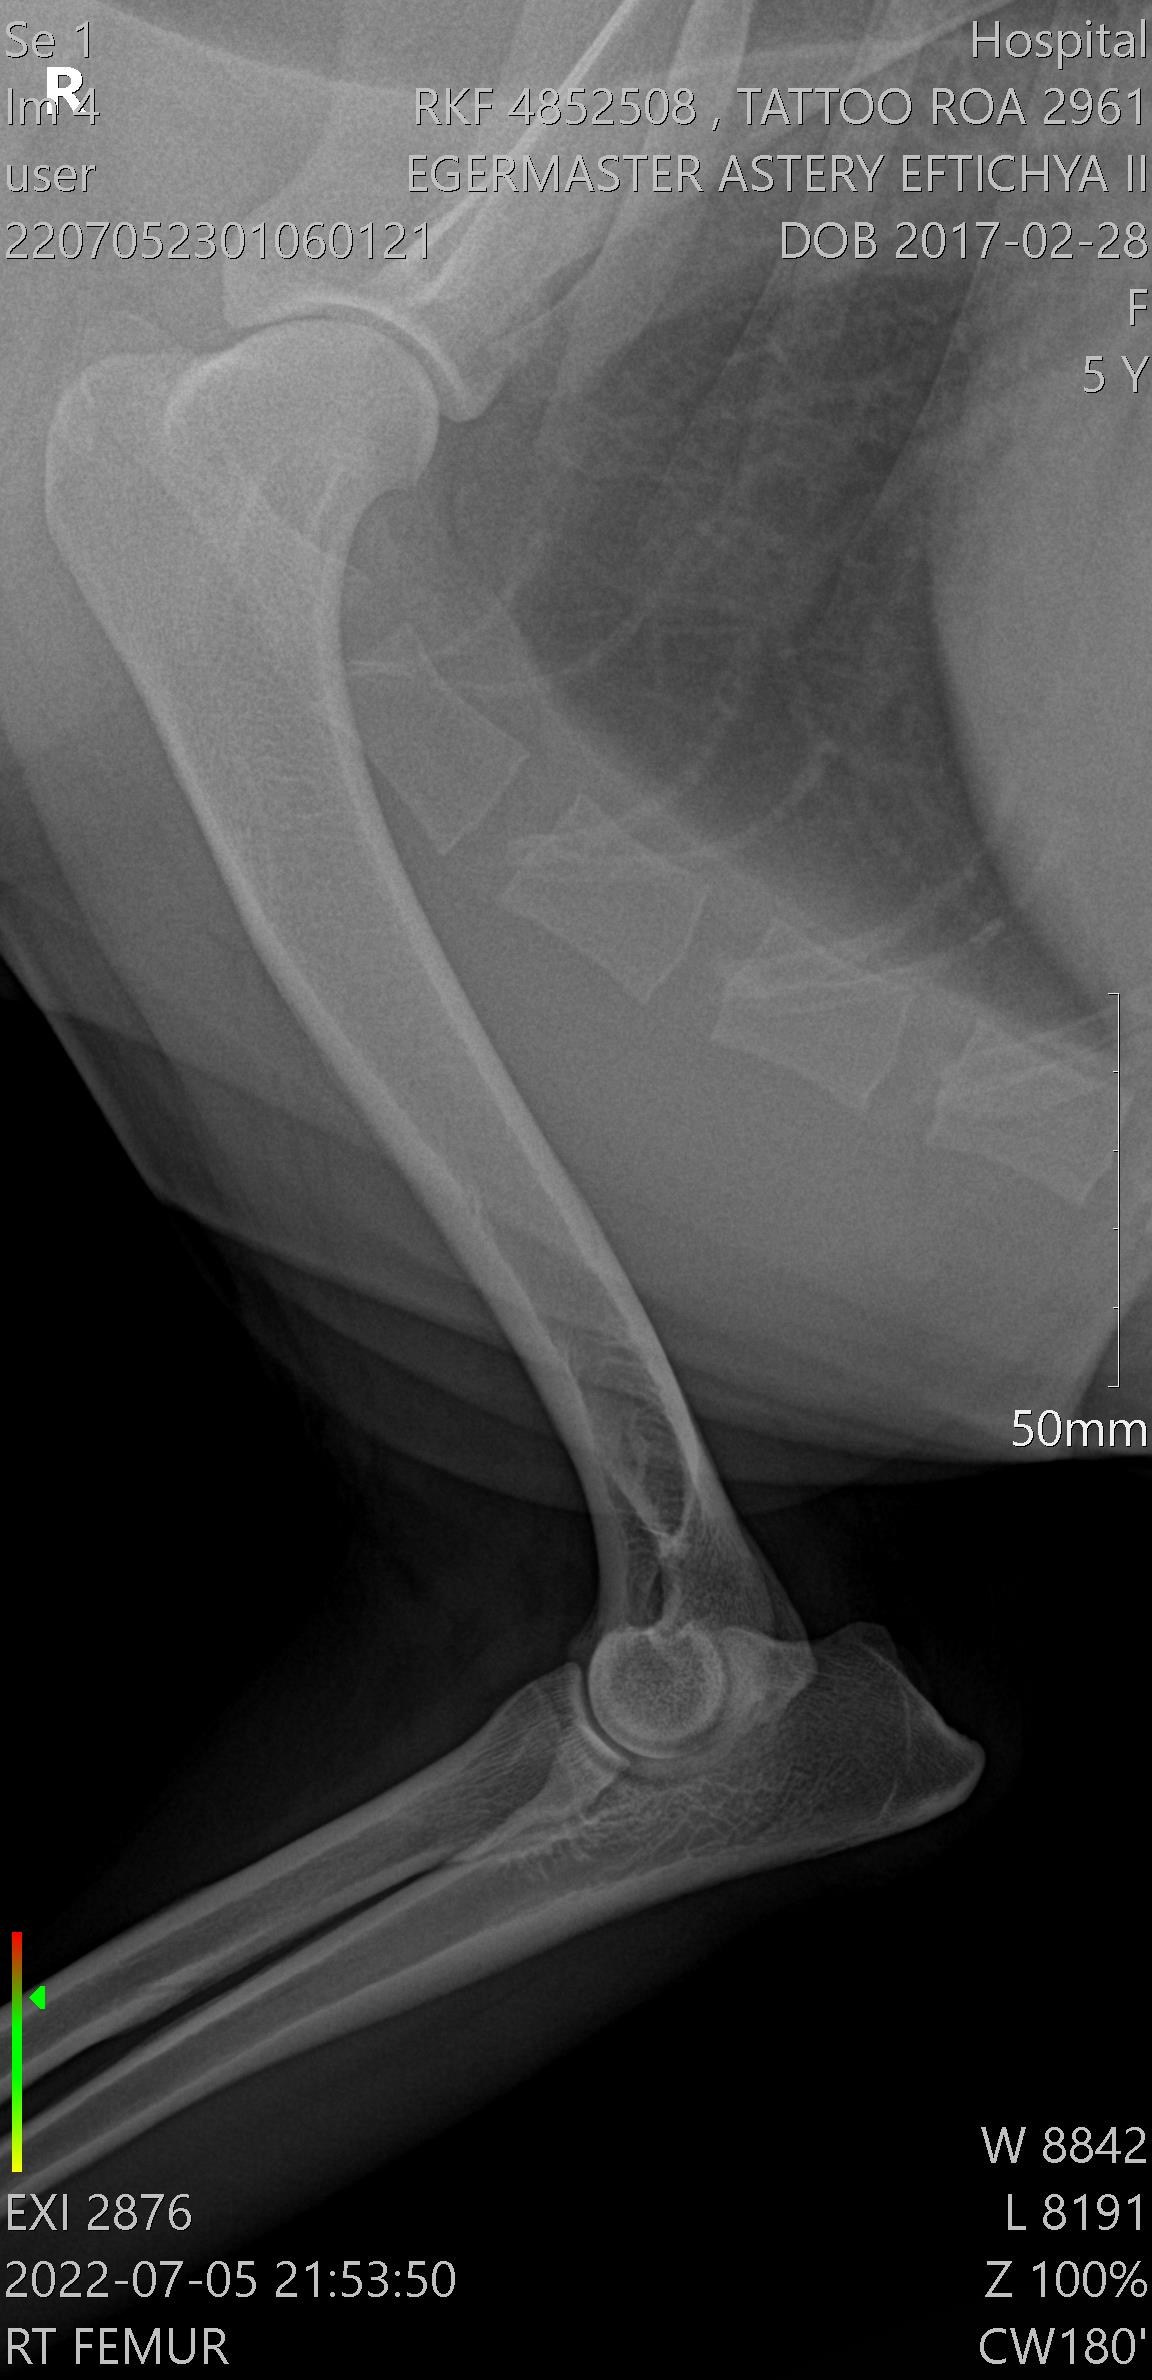

Егермастер Астери Эфтихия ll